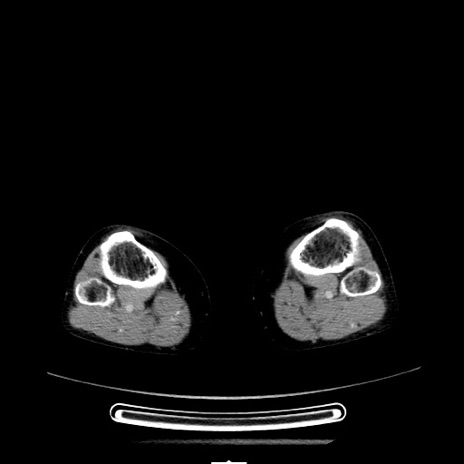

【症例】70歳代女性

【主訴】お腹が張る

【現病歴】1週間くらい前から腹部膨満の自覚あり。昨日夜から増悪したため、本日救急外来受診。

【身体所見】意識清明、BT 36.5℃、BP 165/106mmHg、HR 80bpm、SpO2 98%、腹部:膨満、軟、自発痛・圧痛なし、触診にて不快感あり、腸蠕動音:減弱

【データ】WBC 12600、CRP 1.04